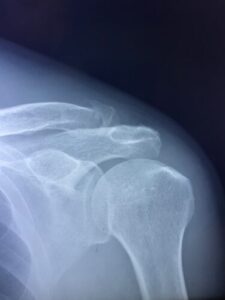

さわやか千葉県民プラザ(肩関節脱臼)